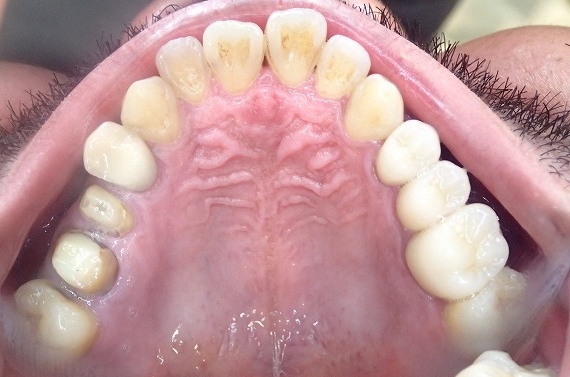

左上 一本スクリューピン 2本根管処置中

左側、一本はスクリューピンが入っており、2本は根管治療の途中です。

最初は上顎左側のジルコニアクラウン製作

すでにファイバーコアの装着が終わっています。

左上 ジルコニアクラウン装着